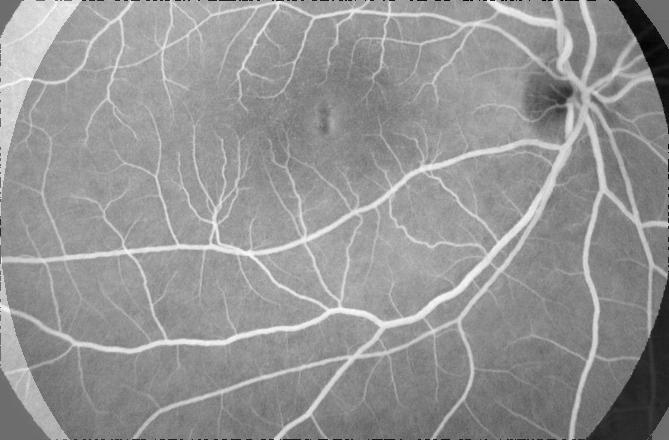

Table 1 shows the registration performance for , our proposed method, and compared with the following methods: - the CNN based registration method of [28]; - an iterative NMI based registration method [85, 86, 87, 88, 89, 90, 91]; and - without deformation consistency constraints. has the best performance across all metrics. Figure 2 shows registration results for retinal images. registers the images closest to the original and is able to recover most deformations to the blood vessels, followed by , , and . It is obvious that deformation reversibility constraints significantly improve registration performance. Note that the fundus images are color while the FA images are grayscale. The reference image is a grayscale version of the fundus image.

| (a) | (b) | (c) | (d) | (e) | (f) | (g) | (h) |